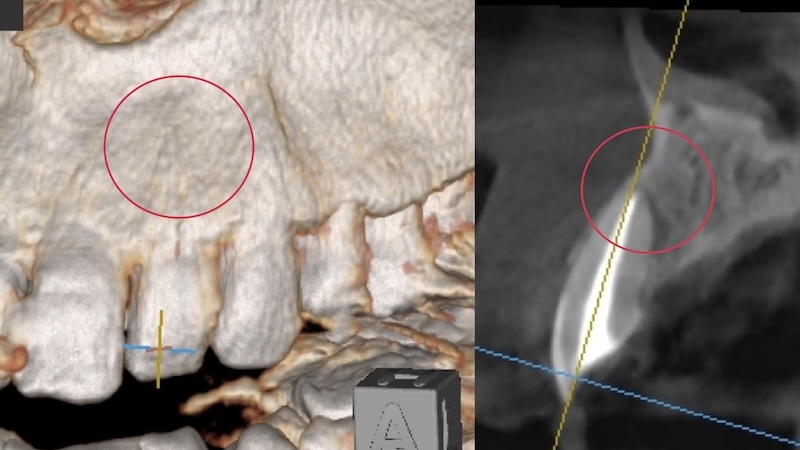

当院で精密検査を行ったところ、確かに状態は良くありませんでした。

しかし、再根管治療(根の再治療)で改善できる可能性は十分にある状態でした。

全体の骨や歯の状態を2Dで確認するレントゲン

骨の欠損と感染の広がりを確認

半年後、歯科用CTで確認したところ――

👉 骨の欠損がほぼ完全に回復

どこに病変があったのか分からないほど、きれいに治癒していました。